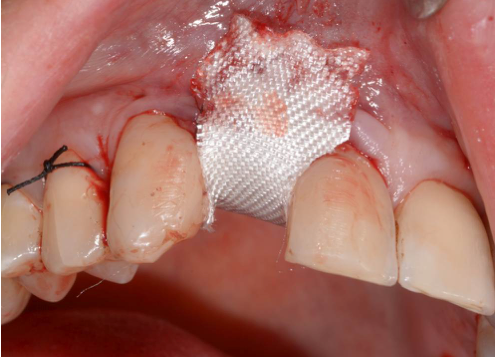

Während oder nach oralen Operationen, von der Extraktion von Zähnen bis hin zu rekonstruktiven Eingriffen, oder Implantationen, bietet BloodSTOP® iX eine schnelle und vorübergehende Kontrolle von Oberflächenblutungen.

BloodSTOP® iX absorbiert schnell Blut und verwandelt sich in ein klares Gel, um die Wunde mit einer transparenten Schutzschicht zu versiegeln, Blutplättchen zu binden und zu aktivieren, sowie die Gerinnung und Wundheilung zu unterstützen.

Anwendungsbeispiele

- Parodontale und chirurgische Wunden